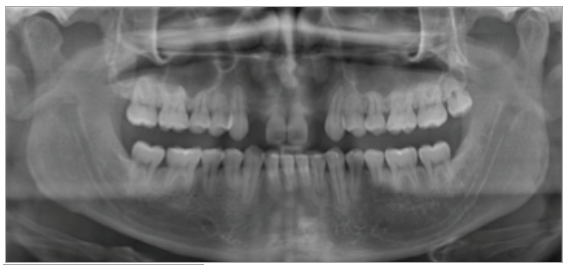

Paciente de sexo masculino de 24 años de edad, de raza mestiza, sin antecedentes sistémicos y oclusalmente estable, que fue transferido al servicio de Rehabilitación Oral del Posgrado y Especialización de la Universidad Peruana Cayetano Heredia, Lima, Perú. Recibió previamente tratamiento ortodóncico en el servicio de Ortodoncia y Ortopedia Maxilar por 6 años. Al examen intraoral presentó agenesia de las piezas 12 y 22 con evidencia de defectos óseos, presenta fenotipo periodontal grueso (figura 1). Al examen radiográfico se observa disminución generalizada de las raíces (Rizomicri), presenta ensanchamiento del ligamento periodontal generalizado (figura 2). Para el plan de trabajo para el diagnóstico se obtuvieron modelos de estudio primario, realizando el encerado para la planificación del tratamiento del sector anterosuperior. Al análisis tomográfico se evidenció poca disponibilidad ósea, motivo por el cual se planificó dos injertos en bloque de mentón con hueso particulado y plasma rico en plaquetas previo a la colocación de implantes dentales (figura 3 y figura 4). Pasado el tiempo de osteointegración (6 meses) se colocaron dos implantes Strong WS Cono Morse (SIN®, Sao Paulo, Brasil) de 3.5 mm x 11 mm. En la segunda fase, se confeccionaron provisionales de acrilico termocurado Vitalloy® (Vitacryl; A. Tarrillo Barba S.A., Lima, Perú) para el manejo de los tejidos blandos a nivel de las piezas 12 y 22, los cuales estuvieron fijados a un cilindro provisional de titanio (SIN®, Sao Paulo, Brasil) atornillado al implante, verificando la adaptación de este al implante mediante una radiografía periapical (figura 5). El cilindro fue recortado dando una altura de 6 mm, los provisionales fueron agujerados en el medio (figura 6), de tal forma que el cilindro calce en el medio del espacio edéntulo, se cubrió la entrada del cilindro con teflón (Golfo USA®) y se capturó el cilindro con acrílico de autocurado Duralay color 62 (Reliance Dental Manufacturing LLC, Illinois USA) (figura 7). Después del acrilizado se retiró el provisional, en la parte cervical se realizó un incrementó con resina fluida (Filtek™ Z350XT Flow - 3M ESPE Dental Products. St. Paul, Minnesota, USA) formando el contorno crítico a 2mm por debajo del zenit de los incisivos centrales de tal manera que entre los zenits de los incisivos centrales, laterales y caninos formen una zona triangular. El contorno subcrítico se realizó de forma convexa (figura 7 y figura 8). Se finalizó con el acabado y pulido del provisional con gomas de grano grueso (gris) y grano fino (verde) (Politip, Ivoclar-Vivadent; Schaan, Liechtenstein). Se manejó la conformación de los tejidos blandos en 2 citas mediante la adición por capas de resina compuesta (Filtek™ Z350 - 3M ESPE Dental Products. St. Paul, Minnesota, USA) a nivel del contorno crítico y subcrítico a las 2 semanas y 4 semanas de la instalación del provisional (figura 9 y figura 10). Se logró conformar las papilas interdentales, el contorno crítico y subcrítico observando que los tejidos se encontraran estables, sin inflamación, con el color de la encía igual a la encía adyacente; todo esto nos indicó que se podía realizar la impresión definitiva. La instalación final se realizó con coronas metal cerámicas cementadas (figura 11 y figura 12).